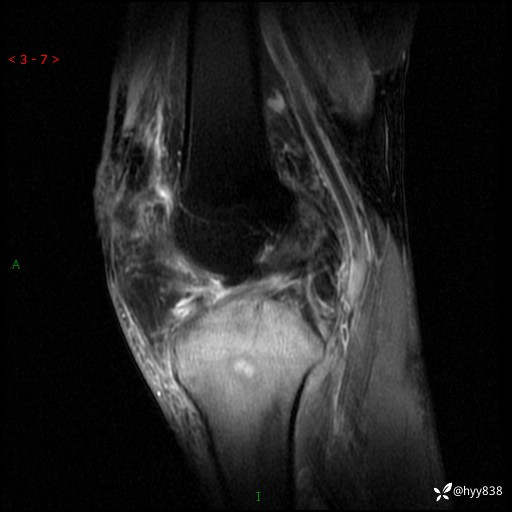

cor T2WIfs

干骺端溶骨性病变病灶周广泛水肿

脓肿

骨母